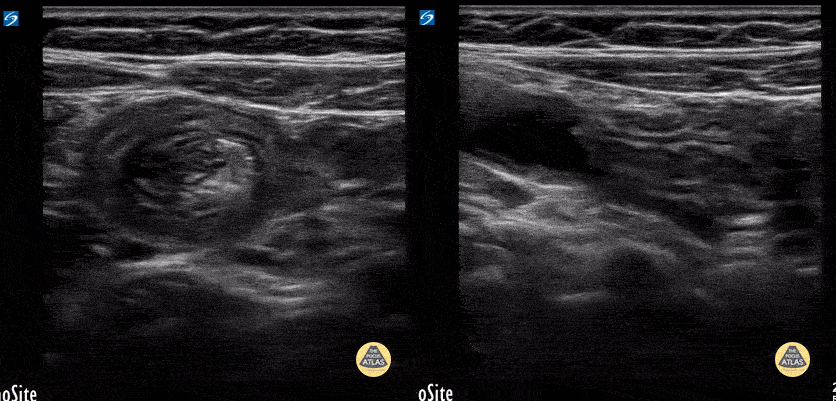

Peds-Gastrointestinal - Ileo-ileal intussusception

7y female with N/V and tactile fever. Benign abdominal exam. Note the small size of the intuss. In long axis you can easily track the bowel wall as it folds into itself and see it is slowly sliding in and out a small bit. Contributor: Matthew Moake, MD PhD